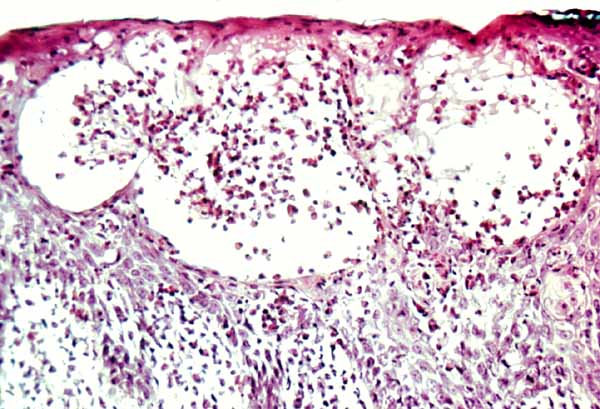

The vesicles seen during the first stage arise within the epidermis and are associated with spongiosis. They are of the type seen in dermatitis . However, they differ from the vesicles of dermatitis by the numerous eosinophils within them and around them in the epidermis (eosinophilic spongiosis) . The epidermis between the vesicles often shows single dyskeratotic cells and whorls of squamous cells with central keratinization. Like the epidermis, the dermis shows an infiltrate containing many eosinophils and some mononuclear cells.